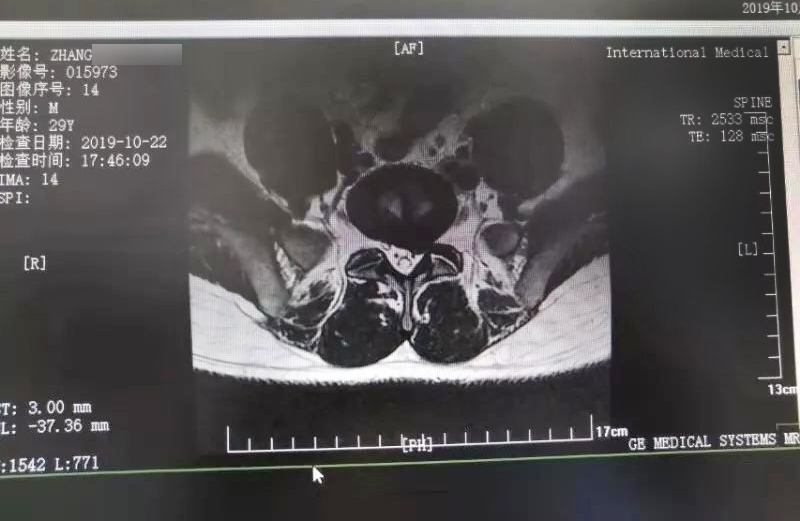

三秦網(wǎng)報道—西安國際醫(yī)學(xué)中心骨科醫(yī)院成功完成首例椎間孔鏡手術(shù)

三秦網(wǎng)報道—西安國際醫(yī)學(xué)中心骨科醫(yī)院成功完成首例椎間孔鏡手術(shù)。點(diǎn)擊閱讀